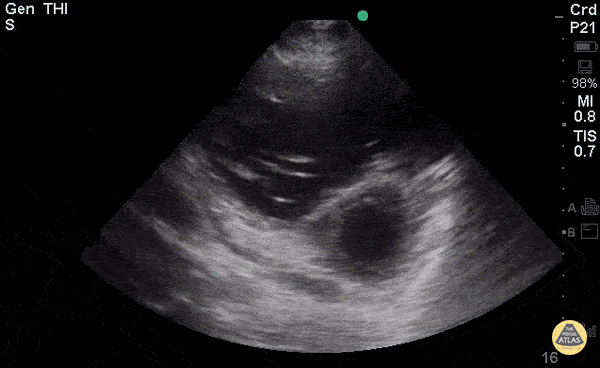

Right Ventricular Dysfunction - Right-Sided Heart Failure (PSAX)

Young woman with a history of Idiopathic Pulmonary Arterial Hypertension with resultant R heart failure who came in short of breath. Greg Powell, MD